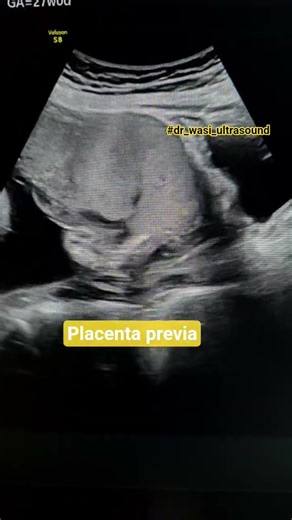

Praevia - Placenta Previa

Previa - Placenta Previa

Percreta Ultrasound - Placenta Previa

Placenta Previa On Ultrasound - Ultrasound

Placenta Ultrasound - Placenta Previa